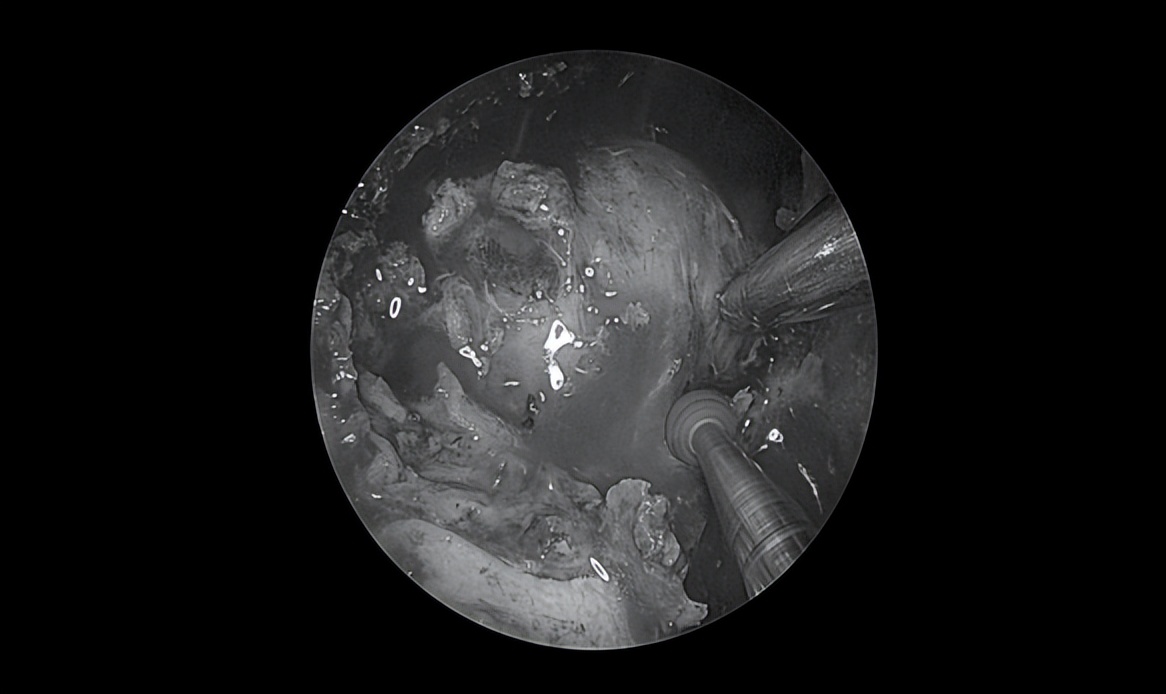

显露中颅窝底肿瘤

沿肿瘤包膜磨除肿瘤周边骨质,充分暴露肿瘤边界

切开肿瘤包膜后,可见大量豆渣样物

清除豆渣样物,显露岩骨段颈内动脉